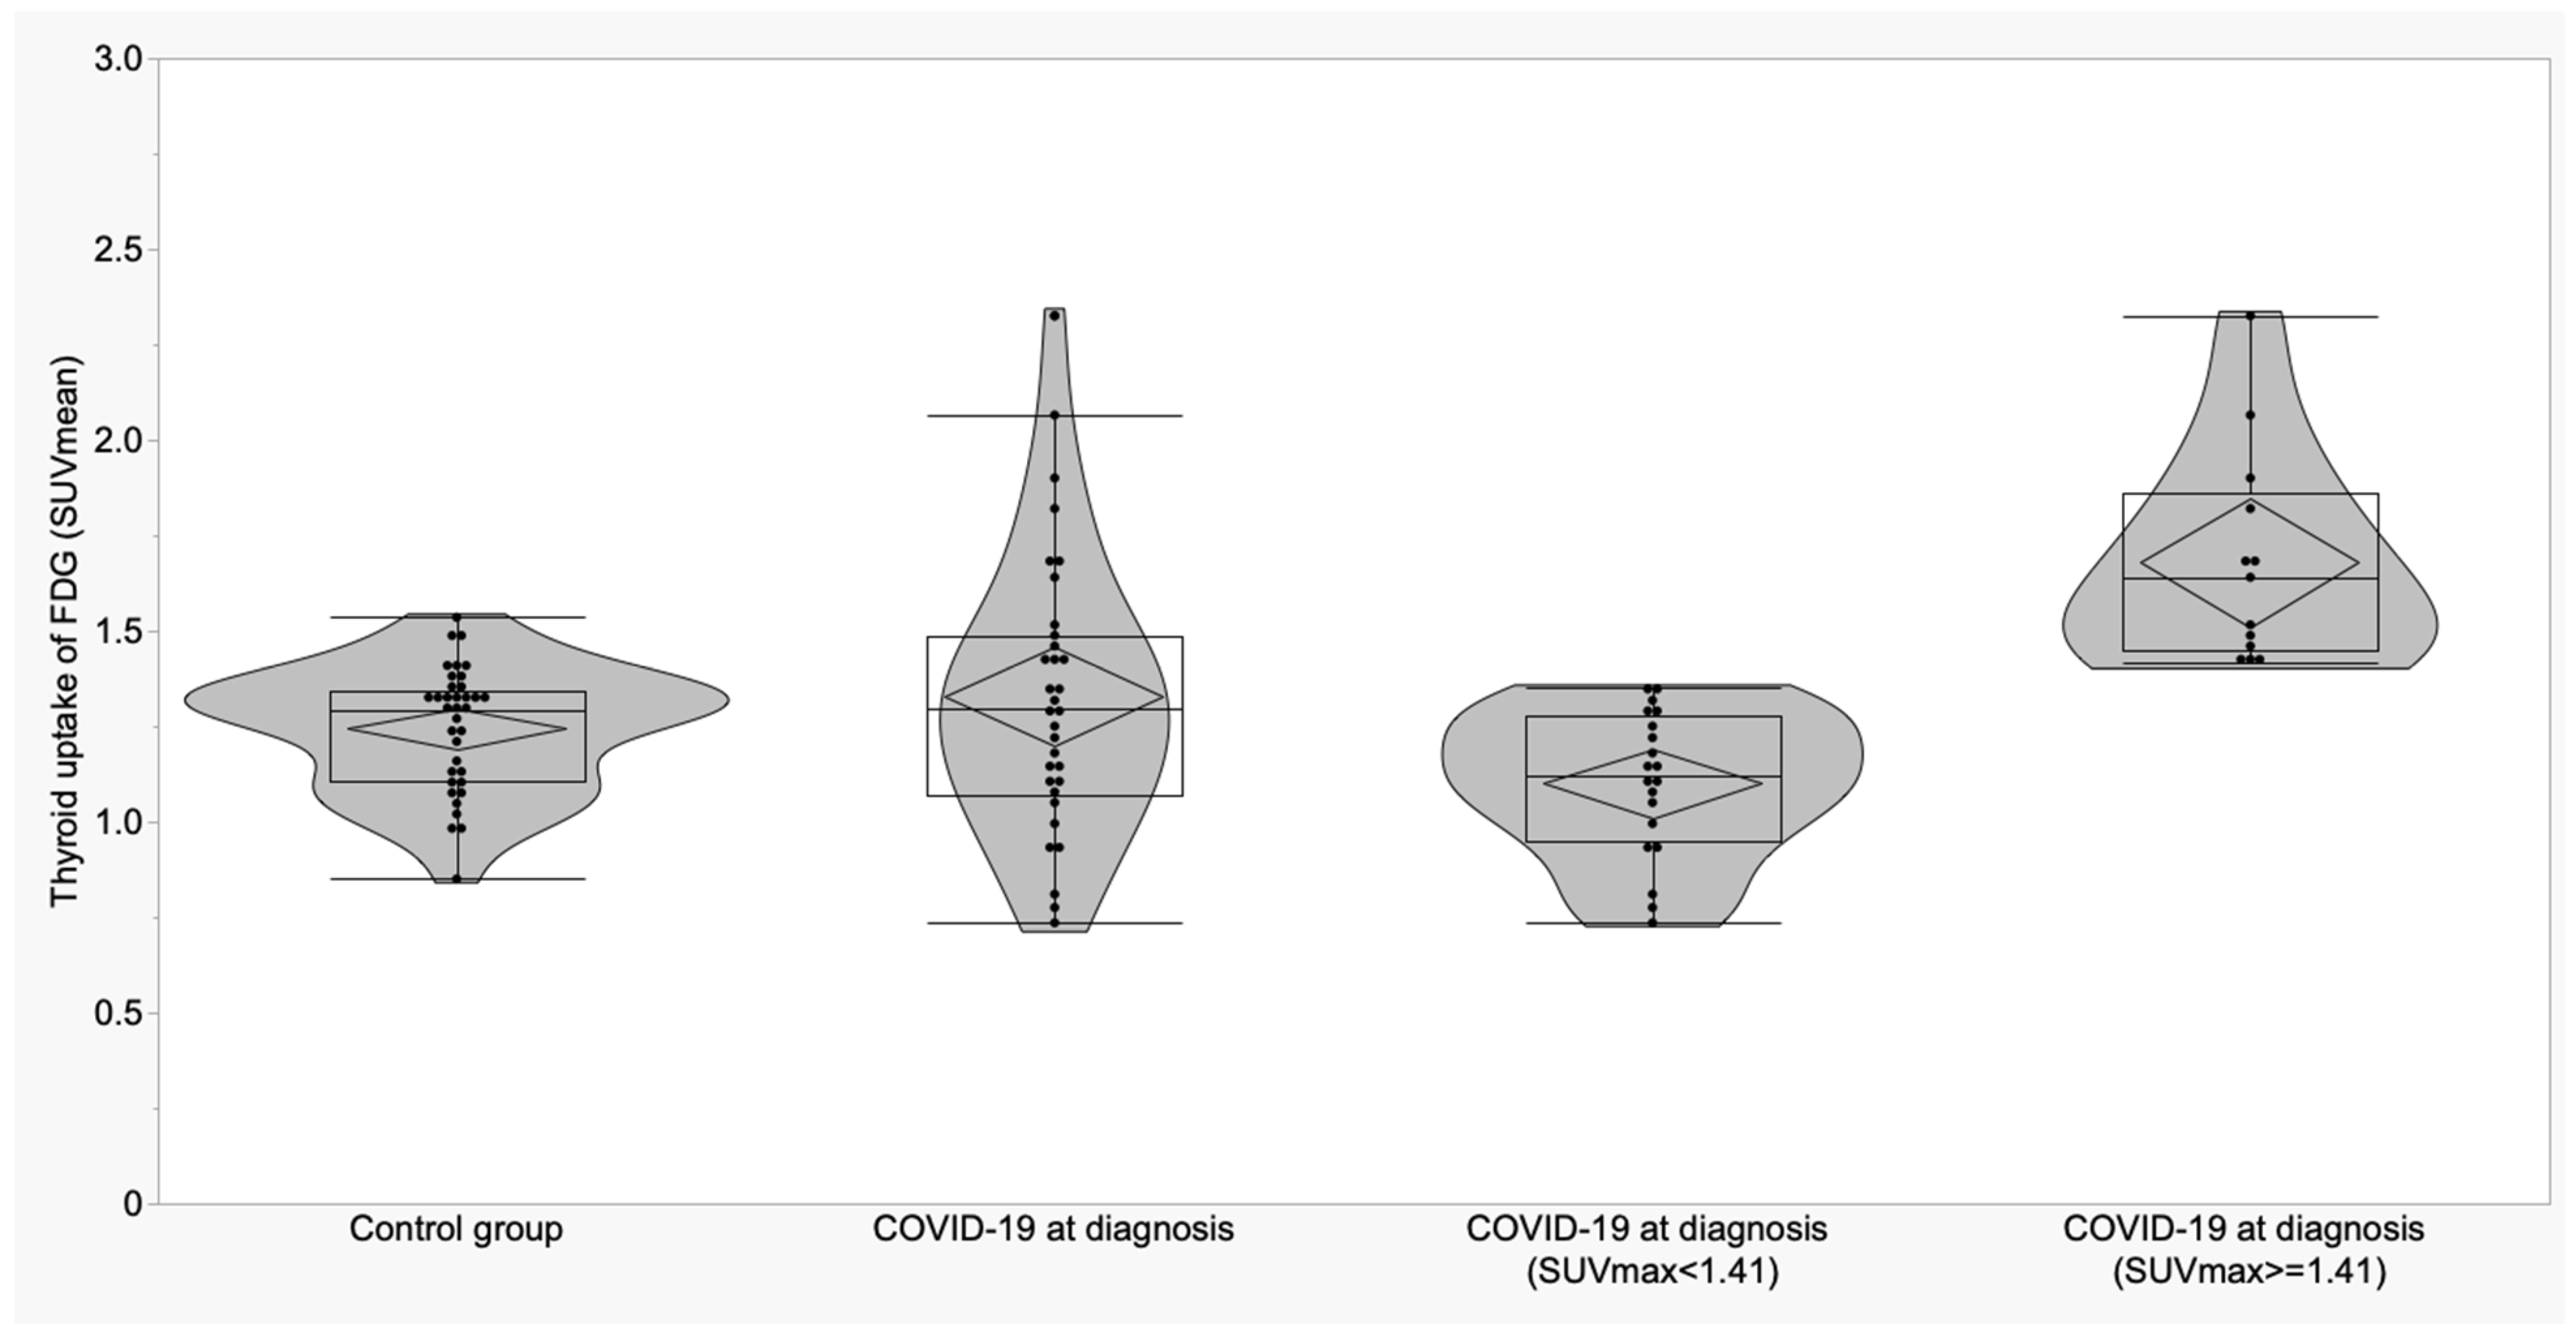

3.2. Thyroid and Adrenal Gland Analysis

| Thyroid (SUVmean) | 1.24 ± 0.16 (1.19 to 1.30) | 1.35 ± 0.38 (1.21 to 1.50) | 1.18 ± 0.22 (0.90 to 1.45) | 0.19 | -- | -- | -- |